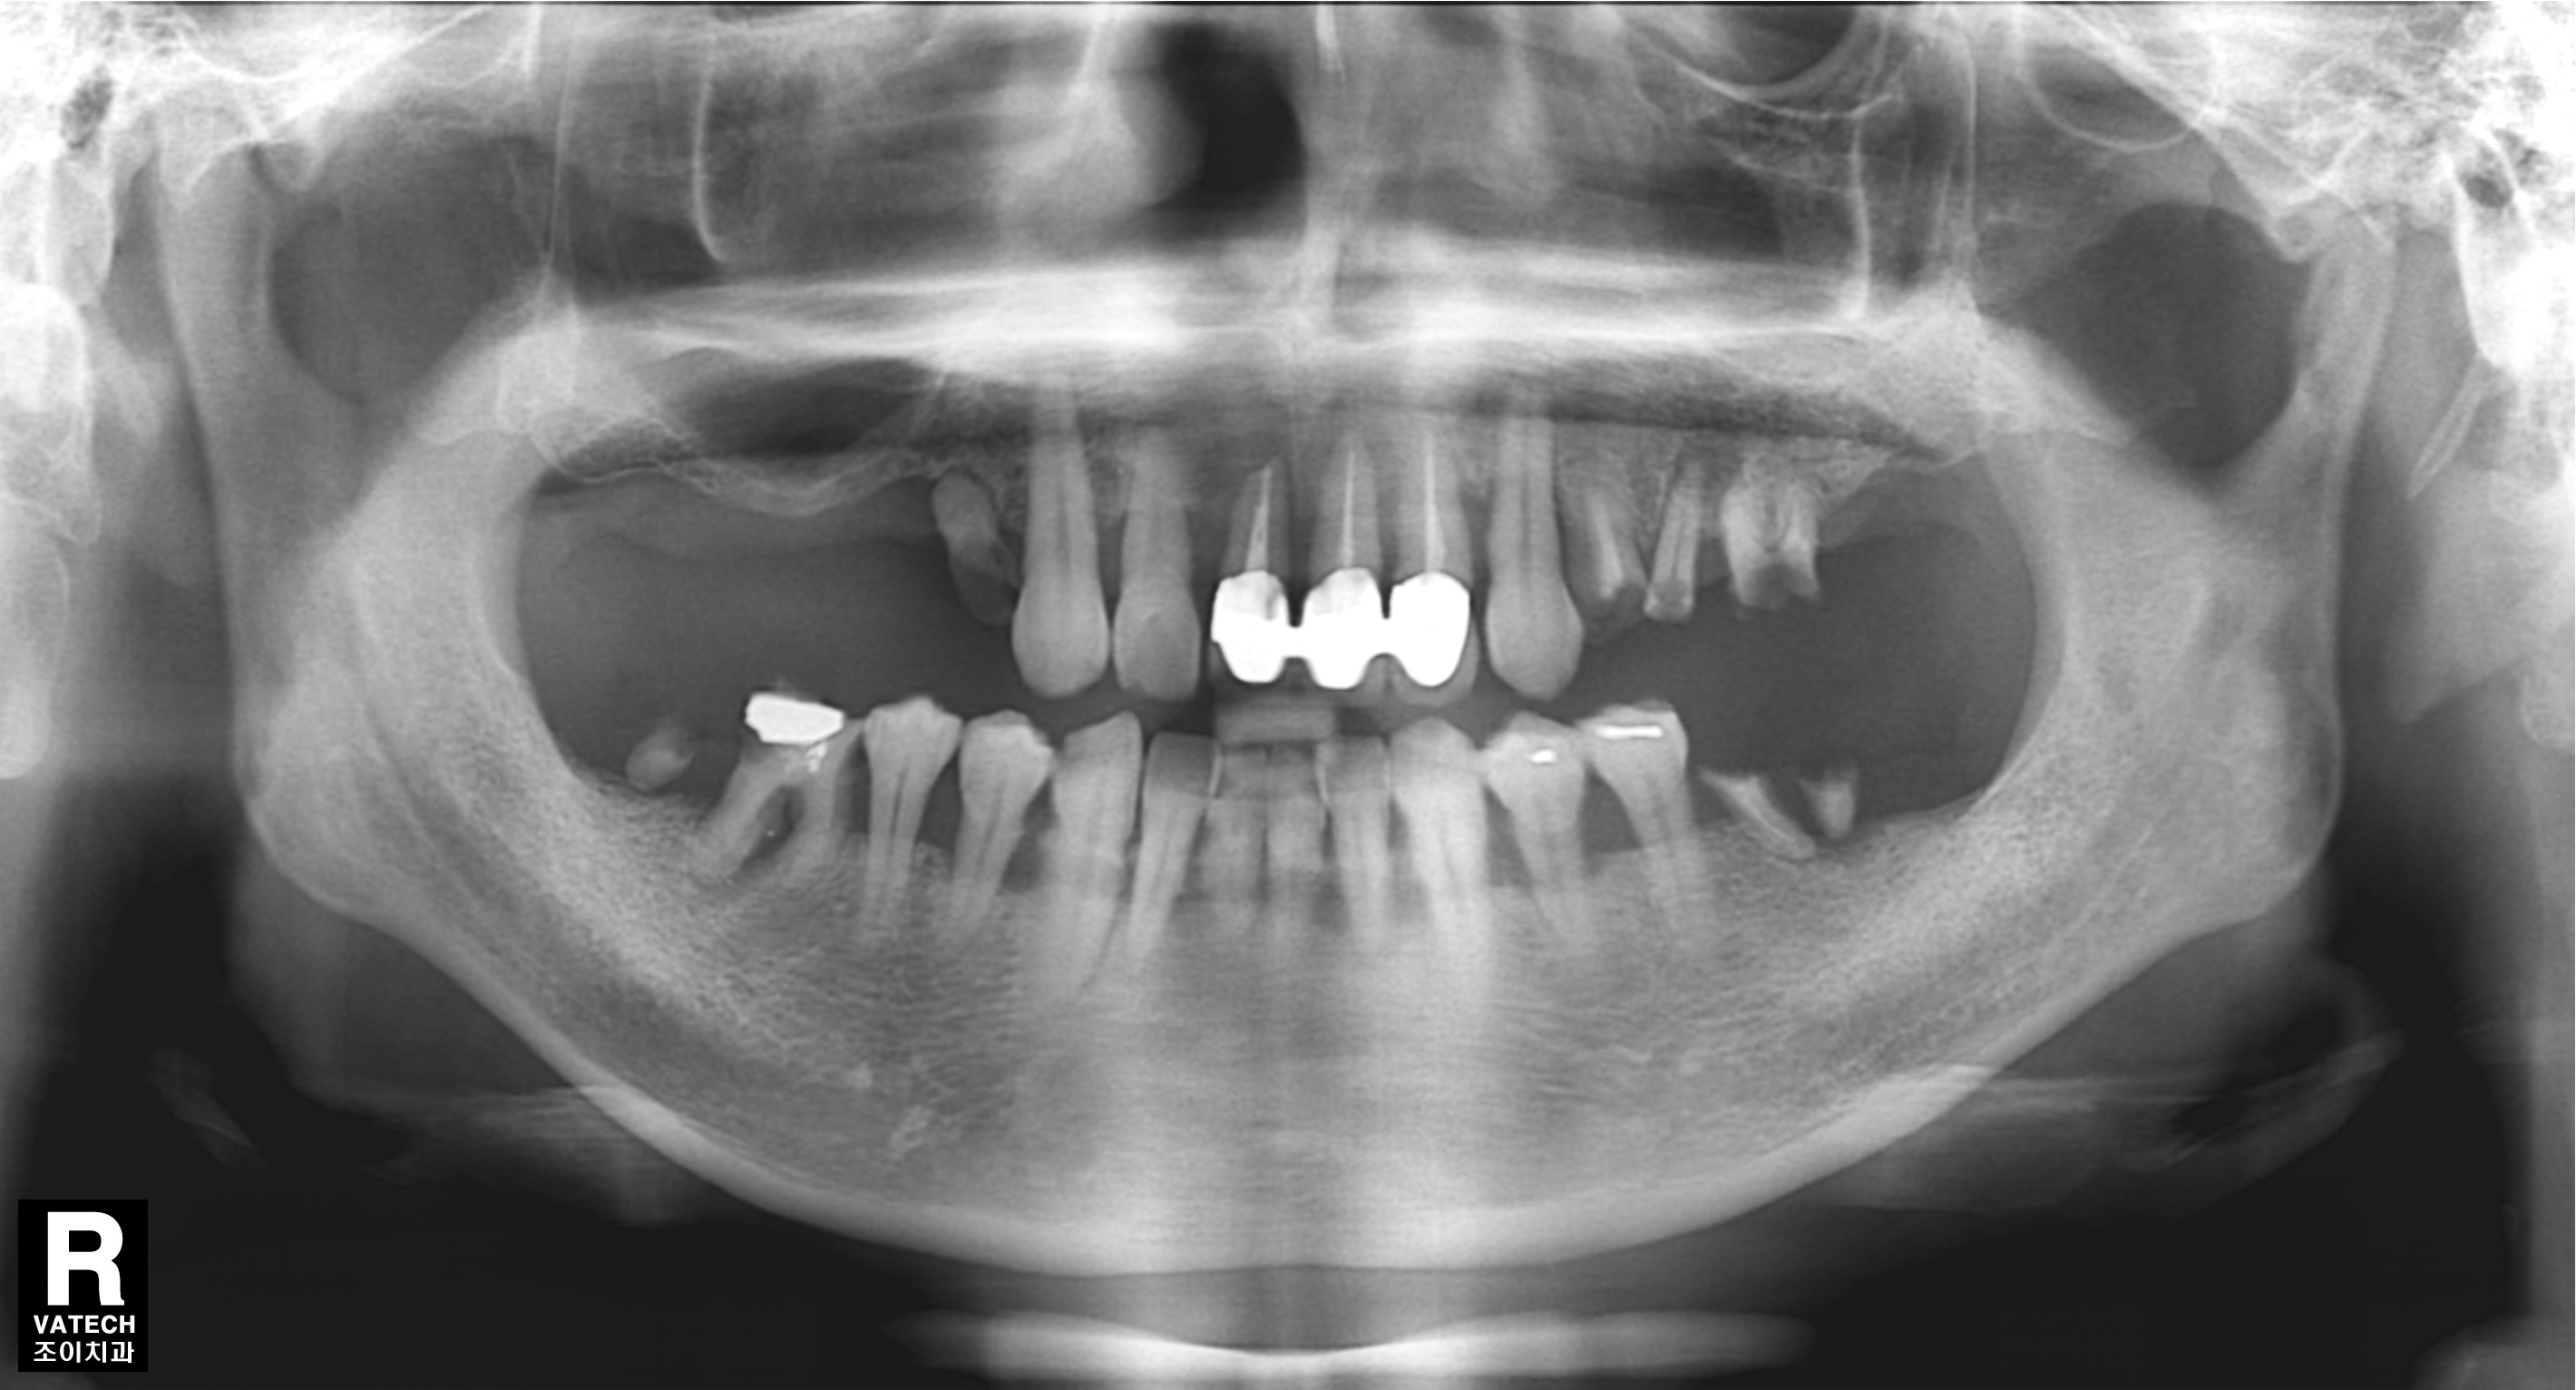

[임플란트] 제목 : 전반적 충치-치주질환에 이환된 젊은 환자의 치료

오복 중 하나로 건강한 치아를 꼽습는다.

만일 현재처럼 임플란트와 충치치료를 할 수 없는 시대에 태어났다면, 그리고 젊은 나이에 치아가 모두 상한 경우라면 평생을 살아가는 데 삶의 질은 건치와 비교하여 정말 엄청난 차이가 있을 것 같습니다.